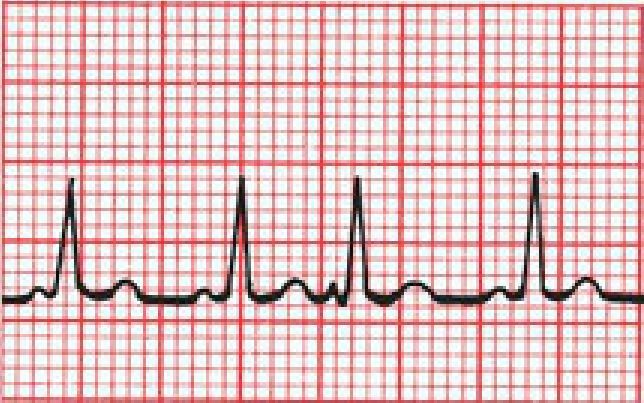

What’s the rate for this one?

The R waves are slightly more than four squares apart—let’s say four and one-quarter. The rate must therefore be between 60 and 75 beats per minute. If you guess 70, you’ll be close. Alternatively, divide 300 by four and one-quarter and get 70.6 beats per minute.